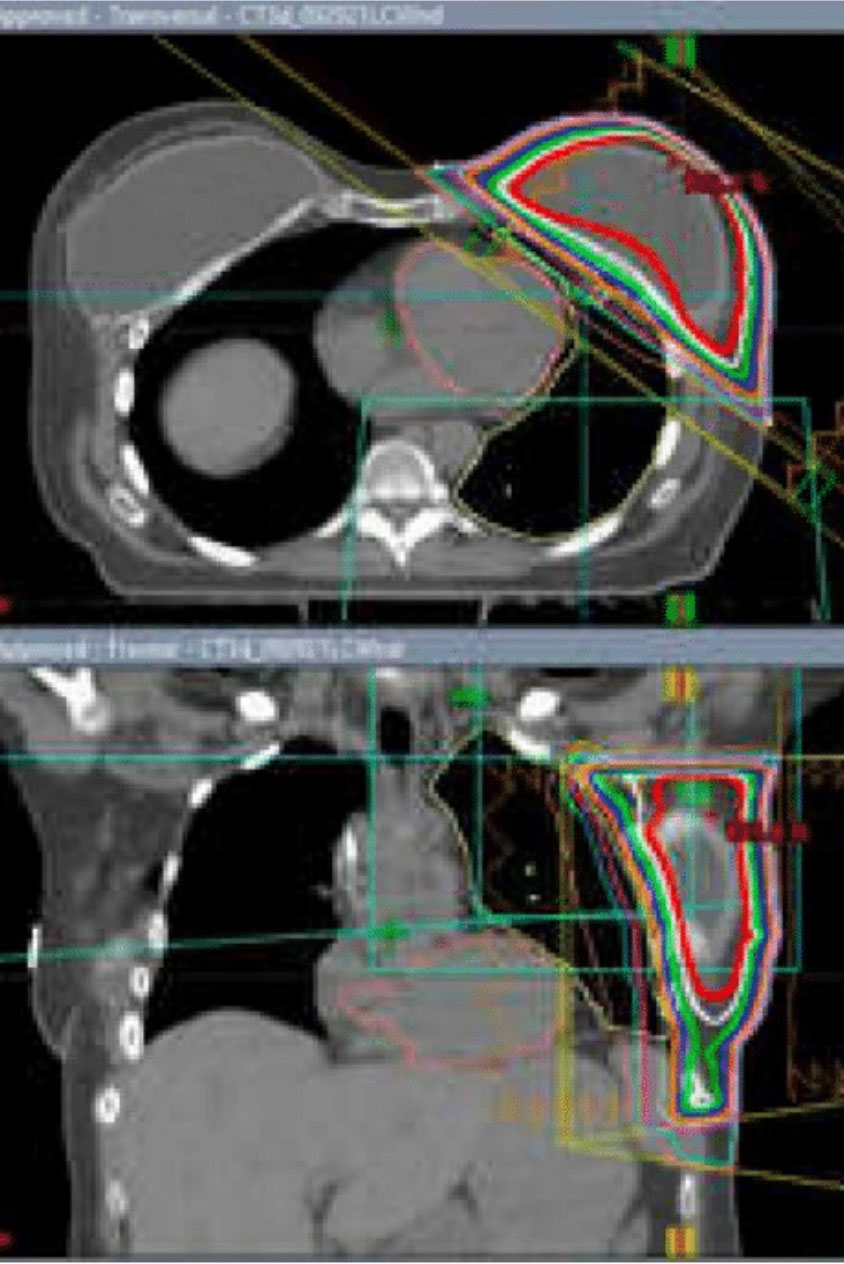

Capital Radiosurgery Centers (CRC) provides highly precise, non-invasive breast cancer treatment using advanced radiation technologies such as stereotactic radiosurgery (SRS), stereotactic body radiation therapy (SBRT), and intensity-modulated radiation therapy (IMRT). Each treatment plan is developed based on clinical appropriateness and delivered by a specialized team of board-certified radiation oncologists, medical physicists, dosimetrists, and oncology-trained nursing and support staff.

These advanced therapies precisely target the tumor area while minimizing radiation exposure to surrounding healthy tissue, including the heart and lungs. Treatment is delivered in a comfortable outpatient setting, allowing patients to receive advanced cancer care close to home without surgery or hospitalization.

SBRT is an advanced radiation therapy that targets tumors with sub-millimeter accuracy. Unlike conventional radiation, which may take weeks, SBRT completes treatment in days—protecting healthy tissue and helping patients maintain their daily routines.

Technology Designed for Precision

We use CyberKnife® and Varian TrueBeam® to treat tumors anywhere in the body, even those that move with breathing or normal motion. Advanced imaging and real-time tracking mean no restrictive frames, no breath-holding, and no invasive procedures.